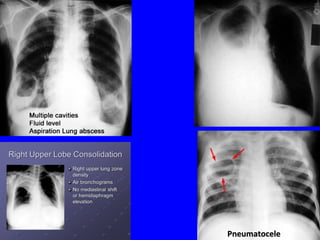

Pneumococcal pneumoniaPneumococcal pneumonia

R upper lobe consolidationR upper lobe consolidation

Air-fluid level in Lung AbscessAir-fluid level in Lung Abscess

Complications of pneumoniaComplications of pneumonia

IntrathoracicIntrathoracic

โ€ข Pleural effusion, empyemaPleural effusion, empyema

โ€ข Collapse, consolidationCollapse, consolidation

โ€ข Lung abscess, pneumatoceleLung abscess, pneumatocele

โ€ข PneumothoraxPneumothorax

PneumatocelePneumatocele